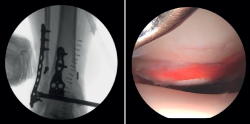

- Assessment of reduction of the posterior malleolus: arthroscopy can be used to verify reduction of the posterior malleolus(5) (Figure 2).

Lee has described a novel technique using a drill guide with ankle arthroscopy for the reduction of joint fragments in posterior malleolus fractures. In particular, this technique is beneficial for patients with trimalleolar fractures who have a depressed joint fragment, as it allows anatomical reduction and minimizes the need for extensive incisions(11). - Extraction of loose bodies. The presence of loose bodies within the joint is a common finding in ankle fractures. One-third of all arthroscopy patients had intra-articular loose bodies removed during surgery (24 out of 71cases)(12). Arthroscopy allows the precise removal of intra-articular loose bodies, which can cause pain, blockage or limitation of mobility, and damage to the joint cartilage(13).